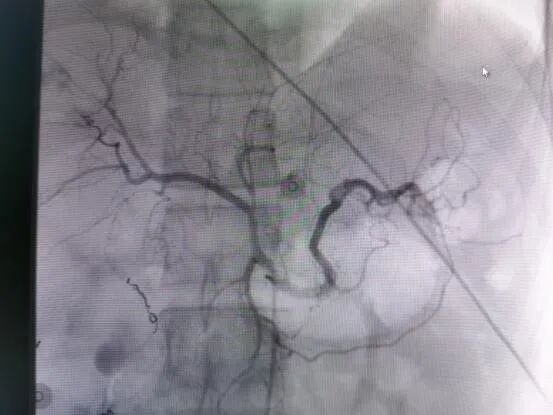

术前DSA造影图,红色箭头指示为出血点

救治方案明确后,患者立即被推入了手术室,在邓文军总监的指挥下,一场惊心动魄、紧张有序的手术开始了。各专科主任严阵以待,在院待命,随时做好开腹手术准备。介入手术由影像中心副主任兼介入组组长吴继雄主任医师亲自主刀,手术过程顺利,术中造影找到右肾脏有几处明显的活动性出血点,肝脏也有两处活动性出血点,给予及时栓塞止血后,再次造影无明显出血。整个手术仅约一个小时,刀口仅针眼大小,术中病人情况稳定,失血量不到10ml,患者成功脱离生命危险,术后被送入ICU密切观察诊治。病情平稳后转入普通病房,经过后续治疗目前该患者已经平安出院,出院时状态良好已经能自行走路。